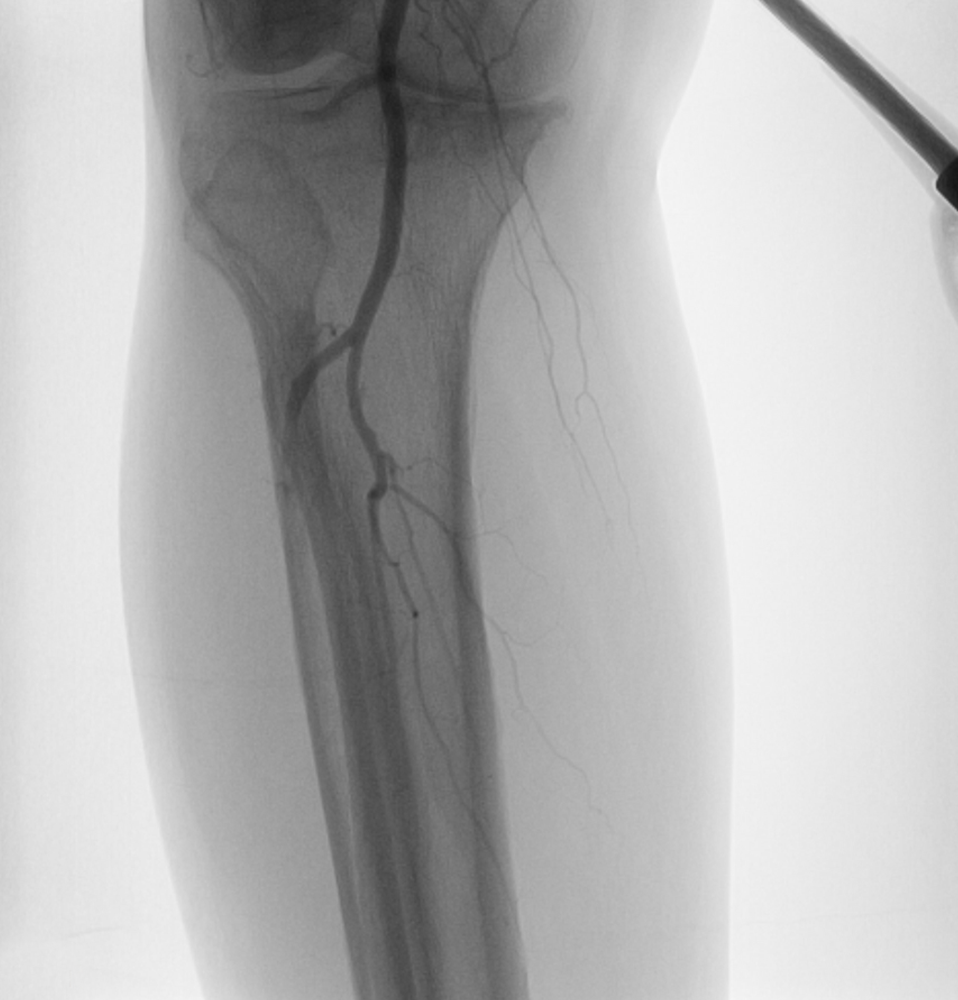

PREOPERATIVE ASSESSMENT AND PREOPERATIVE IMAGING with Duplex scan of lower limb arterial system,CT angiogram and In most patients, standard arteriography is still the “gold standard. If endoluminal therapy is the case, Endoluminal/Endo Vascular treatment at the time of diagnostic arteriography is  performed.

If open bypass is the plan, then  the focus is to visualize potential target arteries and obtain multiple views, as required, to ascertain that no unexpected inflow disease is present that would require treatment before proceeding with Infra inguinal bypass. Although most claudicants require only femoropopliteal bypass, a high proportion of patients with CLI require tibial or pedal bypass. Patients with CLI generally require intervention, since patients with CLI pose a more complex problem because there is a high anticipated amputation rate without lower extremity arterial reconstruction.

Thus, a patent anterior tibial or posterior tibial artery in direct continuity with the foot and pedal arch would be chosen. The preferred conduit for Bypass surgery is Autogenous Vein graft (Saphenous vein)

Particularly in diabetic patients with leg ulcers or Gangrene, emphasize on the importance of restoring a pedal pulse and maximizing forefoot reperfusion adds tremendous value in maintaining graft patency and limb salvage.